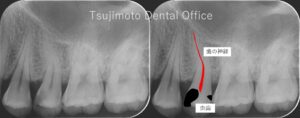

神経を残す治療方針

当院では、安易に神経を抜いたり歯を削ったりせず、可能な限り「ご自身の歯」や「歯の神経(歯髄)」を残すことを大切にしています。

マイクロスコープを活用した精密な診断により、他院で「抜歯・抜髄」と言われたケースでも保存できる可能性を丁寧に検討し、適切な処置をご提案します。